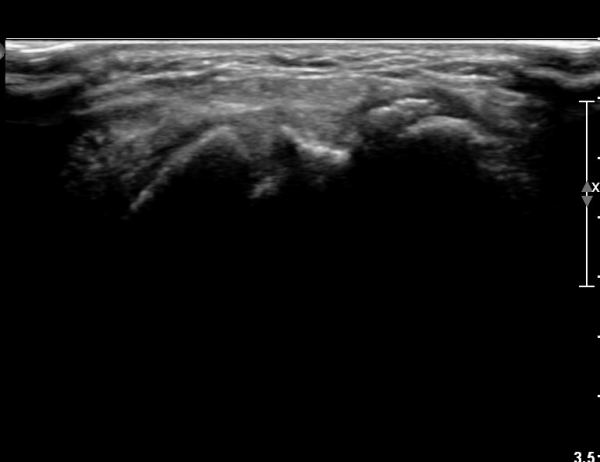

ŽÃËÀÚ¸¦ Á¶±Ù ³»ÃøÀ¸·Î À̵¿ÇÏ´Ï »ï°¢°ñ Ç¥Ãþ¿¡¼ °íÆíÀÌ °üÂûµµ´Ï´Ù(»çÁø 2).